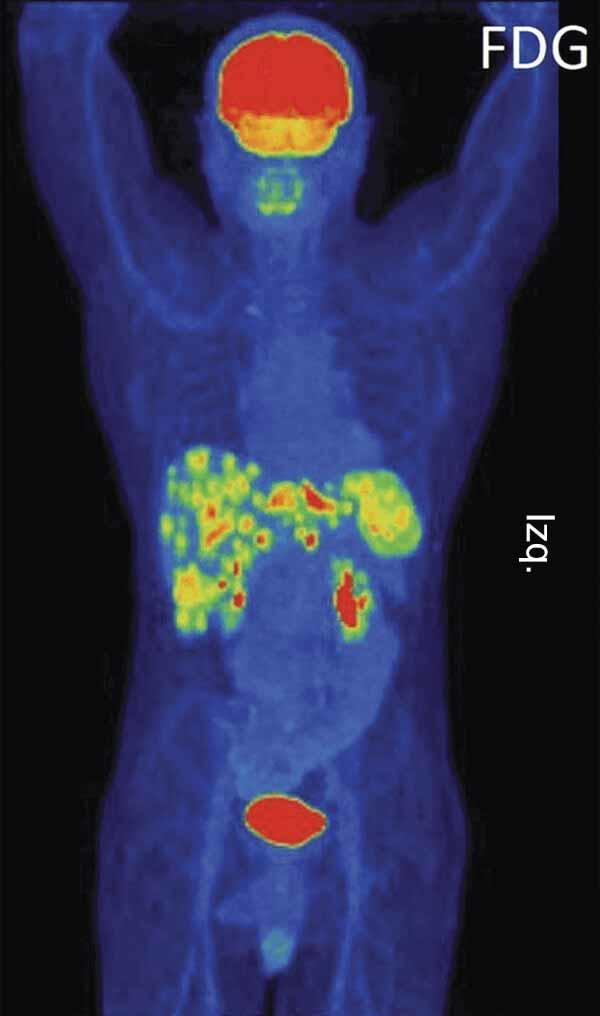

Una exploración con FDG-PET de un paciente con cáncer de la unión gastroesofágica.

Fuente: Li M, Oxford Medical Case Reports Sept. 2014. doi: 10.1093/omcr/omu041.

La aprobación, anunciada el 22 de septiembre, cubre el uso de pembrolizumab en pacientes con cáncer avanzado de estómago o cáncer de la unión gastroesofágica que ha avanzado a pesar de dos o más líneas previas de tratamiento con terapias convencionales. La unión gastroesofágica es un espacio estrecho en donde el esófago se une al estómago.